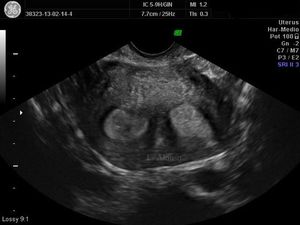

Uterine septa of patients with recurrent pregnancy loss are more vascularized and contain more muscular tissue.